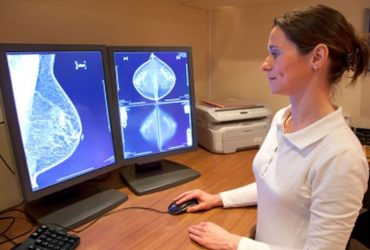

Risk for dying from breast cancer remains elevated 15 years after initial diagnosis